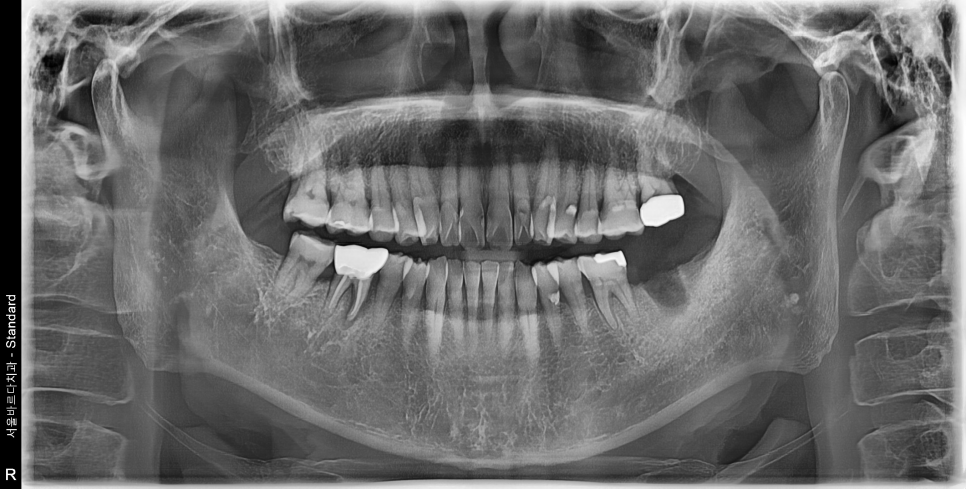

먼저 치과치료의 가장 기본에 해당하는 X-ray들을 보겠습니다.

어금니에 잇몸이 안좋아보이는 부분들이 몇군데 보이는군요.

자세히 보는 작은 X-ray를 추가로 촬영합니다.

흠.. 생각보다 더 많이 심각한 상태입니다.

특히나 뿌리만 남은 치아는 내부에 골소실이 심각한 상태입니다.

한쪽은 치아 머리가 깨져서 검게 뿌리만 남아있고,

한쪽은 뿌리쪽에서 고름주머니가 잡혀있어

건들면 아프고, 매번 안좋은 냄세가 난다고 하시네요.

(촉감이 몰캉몰캉하니 고름이 차있는 상태입니다)

오래전 시행됬을 신경치료의 흔적이 보입니다..

아마 신경치료 후 크라운을 씌우셨을텐데

내부에 충치가 생겨 크라운이 머리채로 부러져나가버렸습니다.

이정도로 치아가 남지 않은 상태면 임플란트 이외에는 방법이 없습니다.